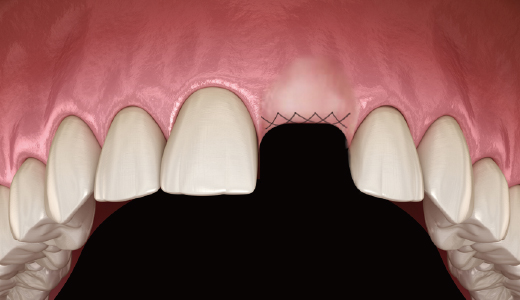

수직 / 수평 골이식 시 : 대량의 골이식재를 Flap 내부로 방해받지 않고 전달

4. Membrane 이식

5. 봉합